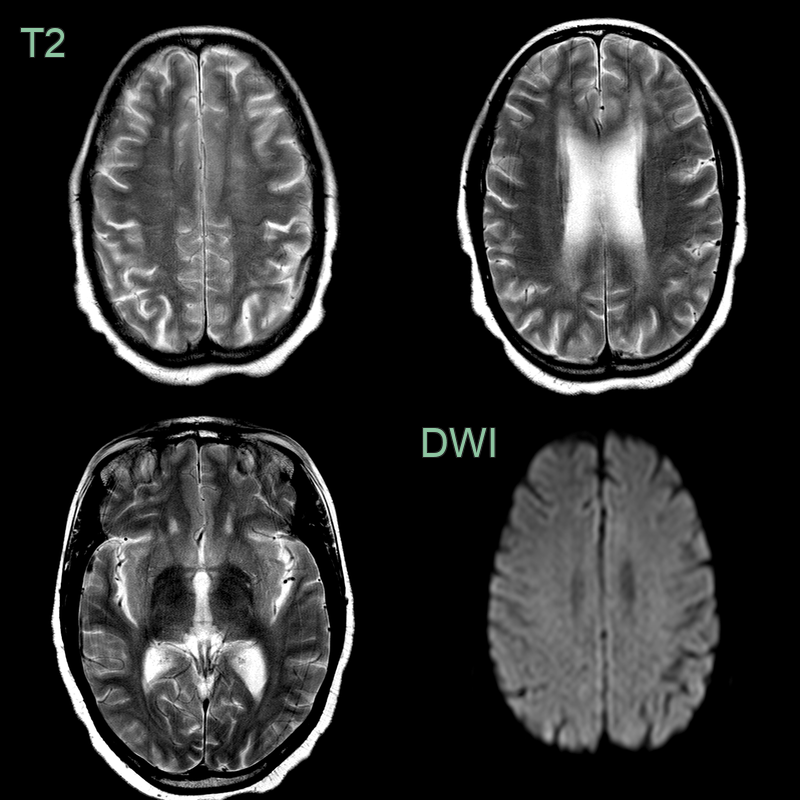

- A 50-year-old patient presented with cognitive impairment.

- A new diagnosis of HIV was made on admission.

- MRI showed patchy diffse white matter hyperintensity without enhancement in both cerebral hemispheres that spared the subcortical U fibres (red arrows).

- Following CSF analysis to exclude other causes and a follow-up scan 1 month later that showed no changes, the findings were ascribed to HIV encephalopathy.